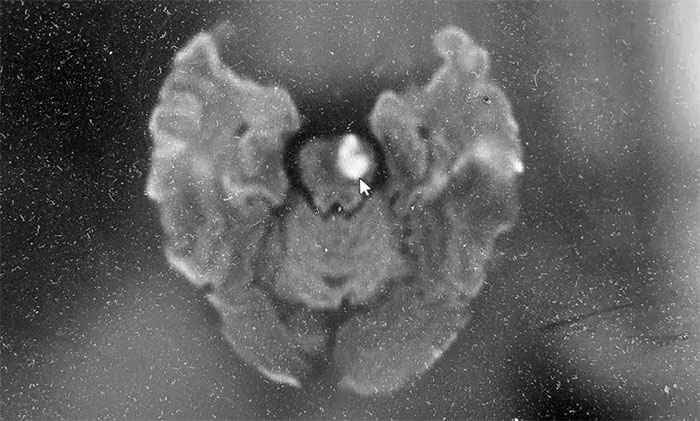

经头颅MRI检查发现,患者脑干及双侧基底节区多发点状及小斑片状异常信号。脑干新发梗塞,偏急性期,进一步定位提示脑穿通动脉闭塞,考虑桥脑腹外侧综合征。

▲ 磁共振检查示:脑干新发梗塞,偏急性期